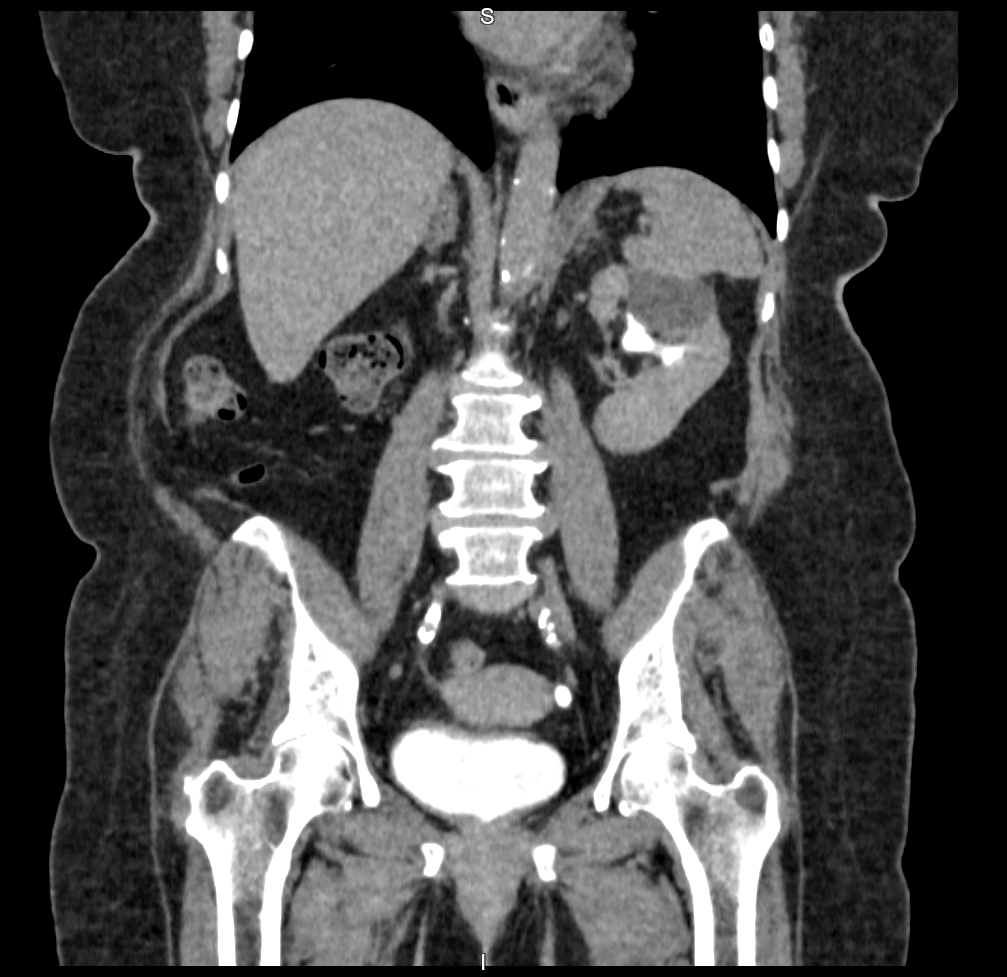

Na tomografia da pelve com uso de contraste, são analisadas as estruturas vasculares da região estudada. A solução de contraste iodado é administrada por via endovenosa e distribui o contraste entre as estruturas com fluxos sanguíneos, realçando as estruturas hipervascularizadas, mostrando, por exemplo, tumores ou processos inflamatórios.